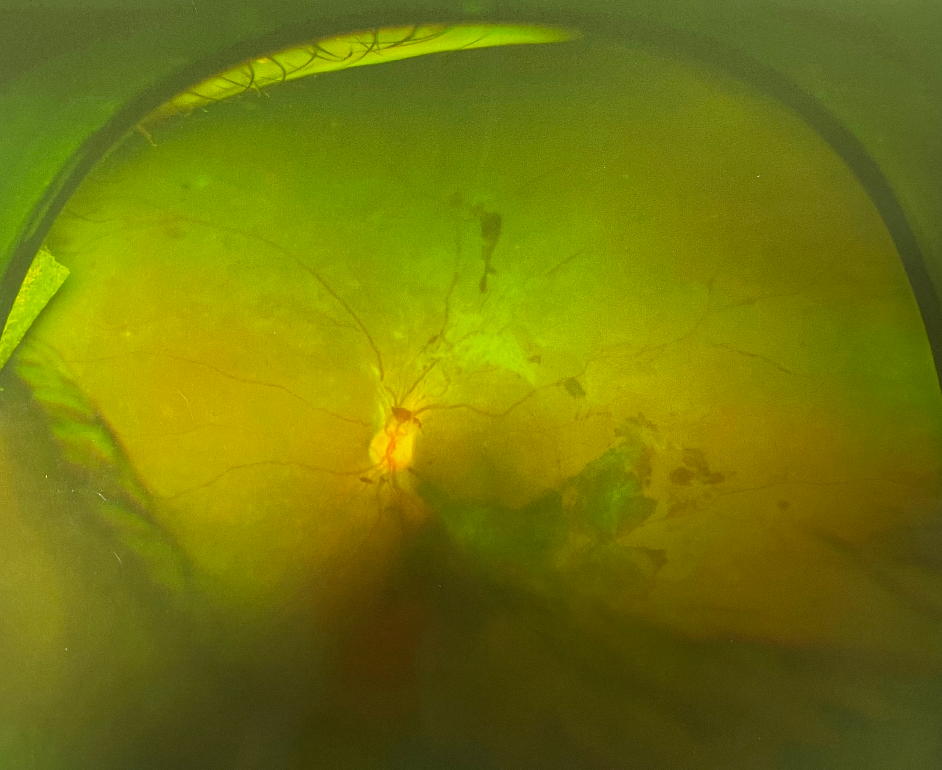

人眼的視網(wǎng)膜血管和脈絡(luò)膜血管系統(tǒng)保障供應(yīng)眼睛能量,并帶走其代謝產(chǎn)物。因此無(wú)論這些血管的哪一部分出問題,都會(huì)影響視網(wǎng)膜的功能。眼底出血是指血液溢出血管到視網(wǎng)膜內(nèi)或周圍,若其范圍大或位于黃斑部則嚴(yán)重影響視力。這種出血需醫(yī)生通過眼底檢查方可看見,一般人是無(wú)法看到的。眼底出血是眼科常見病,既可見于老年又可見于青少年,男女均會(huì)患病。

眼底出血

眼底出血多因高血壓、糖尿病、視網(wǎng)膜血管阻塞或免疫功能異常引起,常見于高血壓視網(wǎng)膜病變、糖尿病視網(wǎng)膜病變、視網(wǎng)膜靜脈阻塞,視網(wǎng)膜靜脈周圍炎性病變。

眼底出血是老年人的常見病,但常常被忽視,原因是其不易被發(fā)現(xiàn),在外觀上看不出來(lái),只能在醫(yī)院眼底鏡下被檢查出來(lái)。老年人易出現(xiàn)眼底出血,原因是老人的血管柔韌性和彈性發(fā)生改變,較硬且脆,稍有刺激便可能出血。伴高血壓、糖尿病、動(dòng)脈硬化、高脂血癥的病人,眼底血管硬化,應(yīng)特別注意。